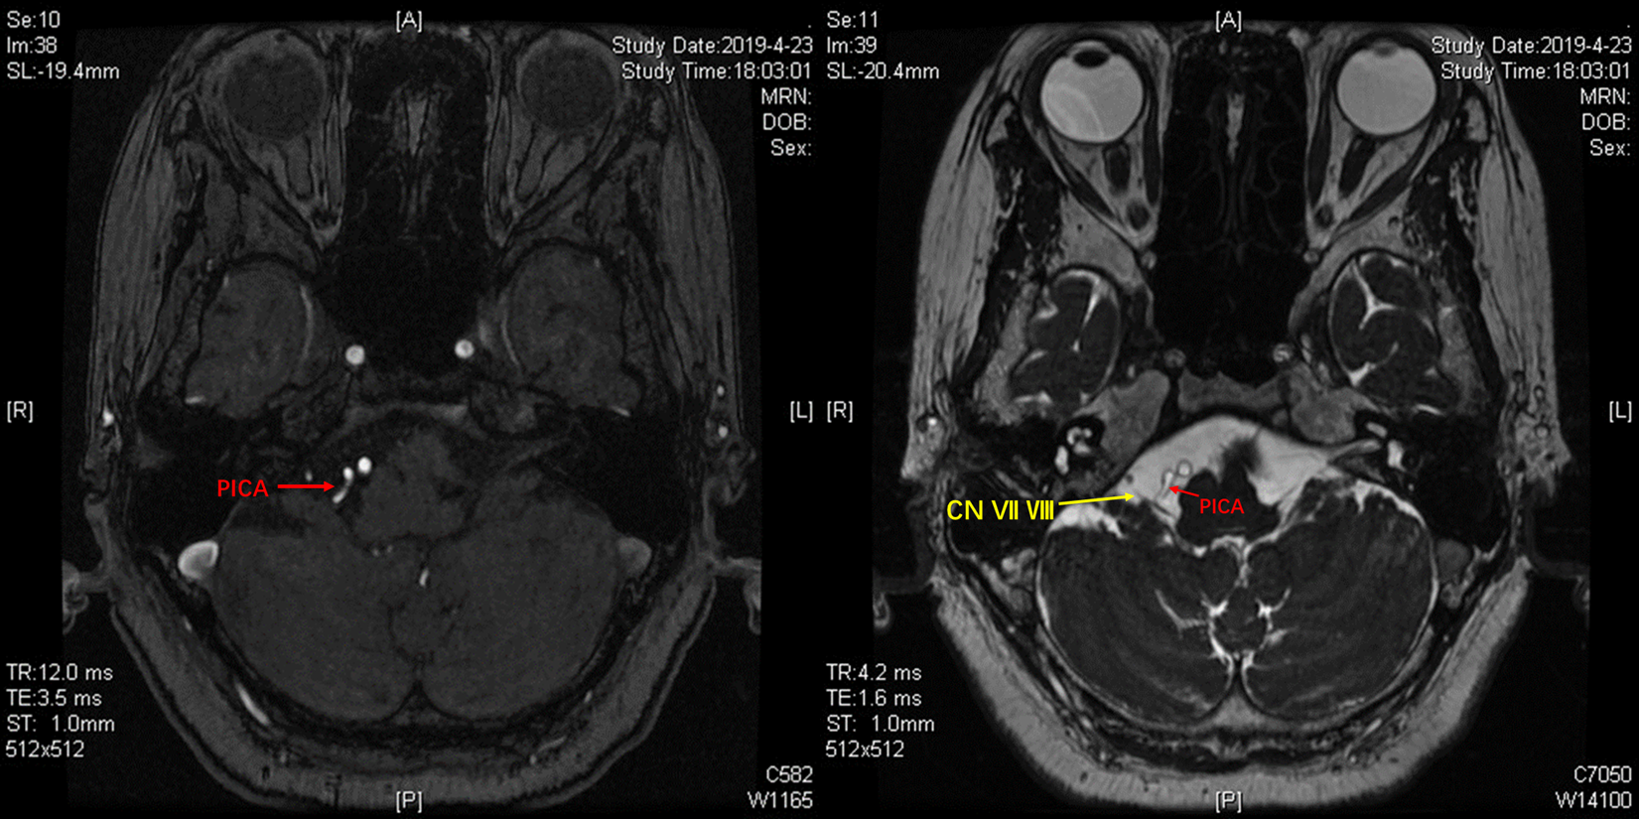

CASE2:右侧面肌痉挛(PICA)

3D-TOF序列提示椎基底动脉迂曲,偏向右侧,小脑后下动脉PICA从劣势椎动脉发出,于上下各成一袢,最后绕回下方,呈“S”型。

TOF序列及FIESTA序列可见PICA在下方的第一个弯曲与面听神经关系密切。

镜下:从面听神经与后组颅神经之间观察迂曲的小脑后下动脉。

神经内镜抵近观察,与术前影像一致,PICA从VA发出后于下方呈袢,压迫面神经出脑干处。

Tefflon垫绵充分减压。再次观察,PICA如我们所见,迂曲呈“S”型,再于后组颅神经后方(手术视角)绕回,与小脑后下动脉走行特点相吻合。

术后恢复良好,未再抽搐。